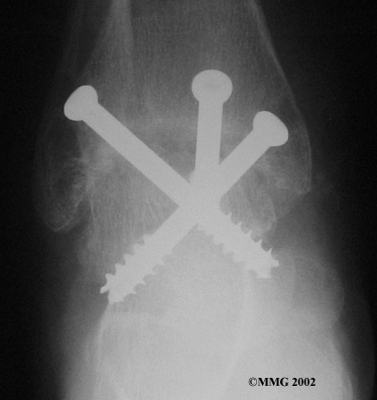

When the ankle joint becomes so painful that it is difficult to walk, surgery may be suggested to fuse the ankle joint. An ankle fusion is sometimes also called an ankle arthrodesis. In this operation, the three bones that make up the ankle joint (the talus, the tibia, and the fibula) are allowed to grow together, or fuse, into one bone. Once this is done the ankle no longer is able to move, but with a successful fusion the pain is gone. Most people with a successful fusion of the ankle are able to walk without much trouble, and in some cases it is almost impossible to tell that the ankle is stiff. But it is very difficult to run because you lose the ability to push off with the toes. The foot can't bend down.

Ankle Fusion

Most people will need some changes made to their shoes following an ankle fusion. Because the ankle no longer moves, it is difficult to roll over the top of the foot when you take a step. For this reason, shoes are usually fitted with a rocker sole. This allows the shoe to roll instead of the foot. A special heel is sometimes built on the shoe to absorb some of the shock.

The ankle fusion is a good operation, especially for a young, active person. It is usually the preferred option for post-traumatic arthritis of the ankle. Once the ankle is successfully fused it can last a lifetime, and no other operations are expected later unless there are problems. But there are complications associated with the ankle fusion, and not all ankle fusions are successful.